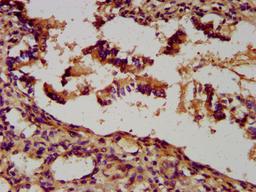

IHC image of CSB-PA025629LA01HU diluted at 1:300 and staining in paraffin-embedded human lung tissue performed on a Leica BondTM system. After dewaxing and hydration, antigen retrieval was mediated by high pressure in a citrate buffer (pH 6.0). Section was blocked with 10% normal goat serum 30min at RT. Then primary antibody (1% BSA) was incubated at 4°C overnight. The primary is detected by a biotinylated secondary antibody and visualized using an HRP conjugated SP system.